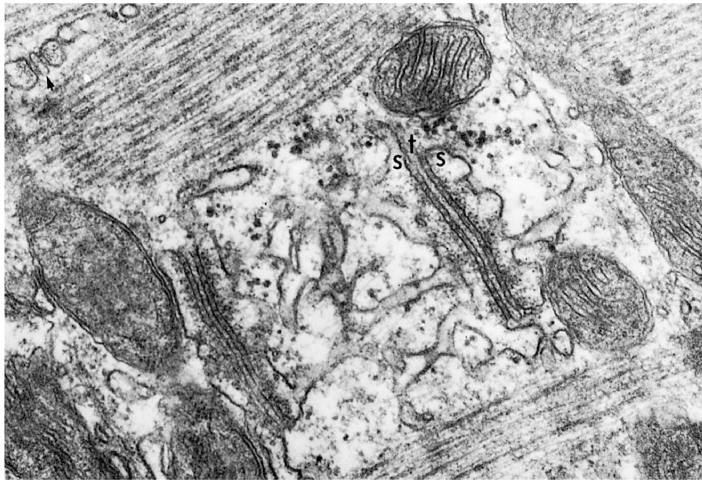

3. Identify the structure labeled s in the above photomicrograph.

A) Desmosome

B) Intercalated disk

C) Triad

D) Mitochondrial cristae

E) sarcomere